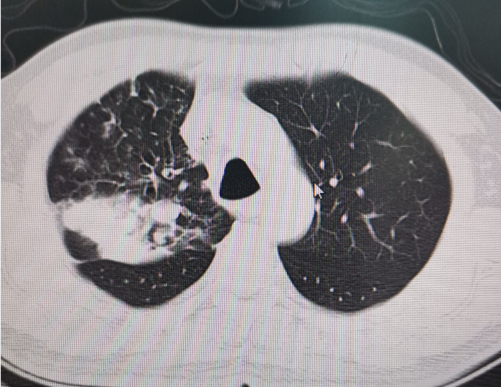

• 肺鳞癌 vs 肺腺癌:一字之差,治疗方案却天差地别!

肺鳞癌 vs 肺腺癌:一字之差,治疗方案却天差地别!

肺鳞癌和肺腺癌占据整个肺癌的大部分,很多患者拿到病理报告,看到这两个名字,可能觉得都是肺癌,治疗差不多。 但实际上,虽然只有一个字不一样,但这两者的差别很大。了解它们,对治疗和康复至关重要。 1 ...【详情】